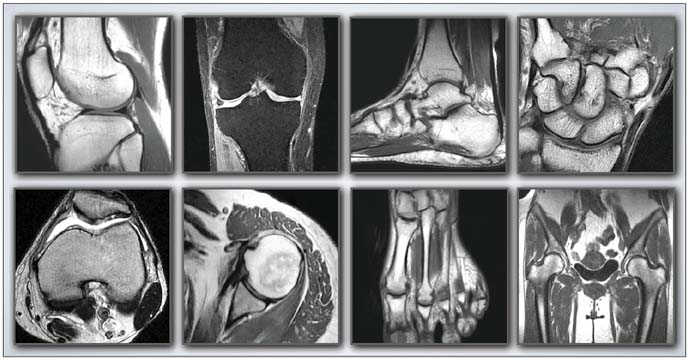

Musculoskeletal Imaging